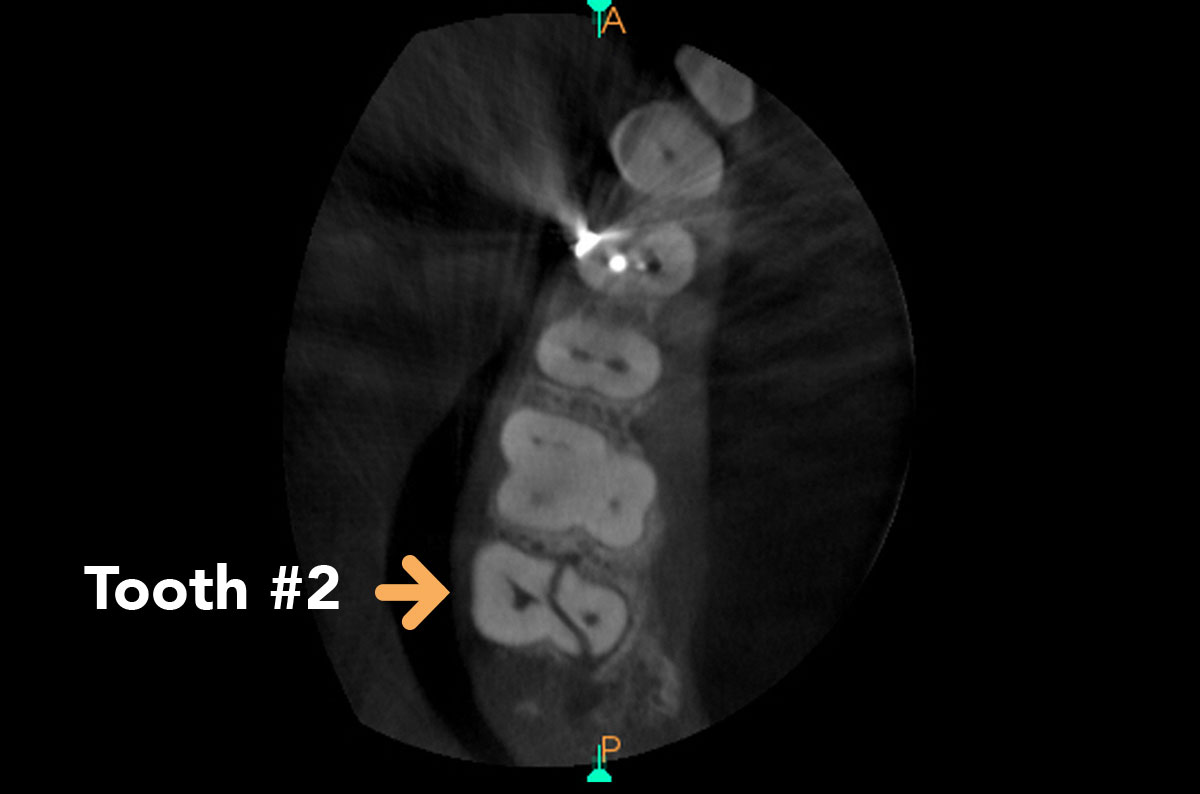

Image showing Axial slice of Tooth 2

Axial slice of the same region showing a definite oblique fracture extending from the midmesial to the distopalatal aspect of tooth #2 where extraction is indicated. Definitive diagnosis saves the patient time and costly exploratory procedures.